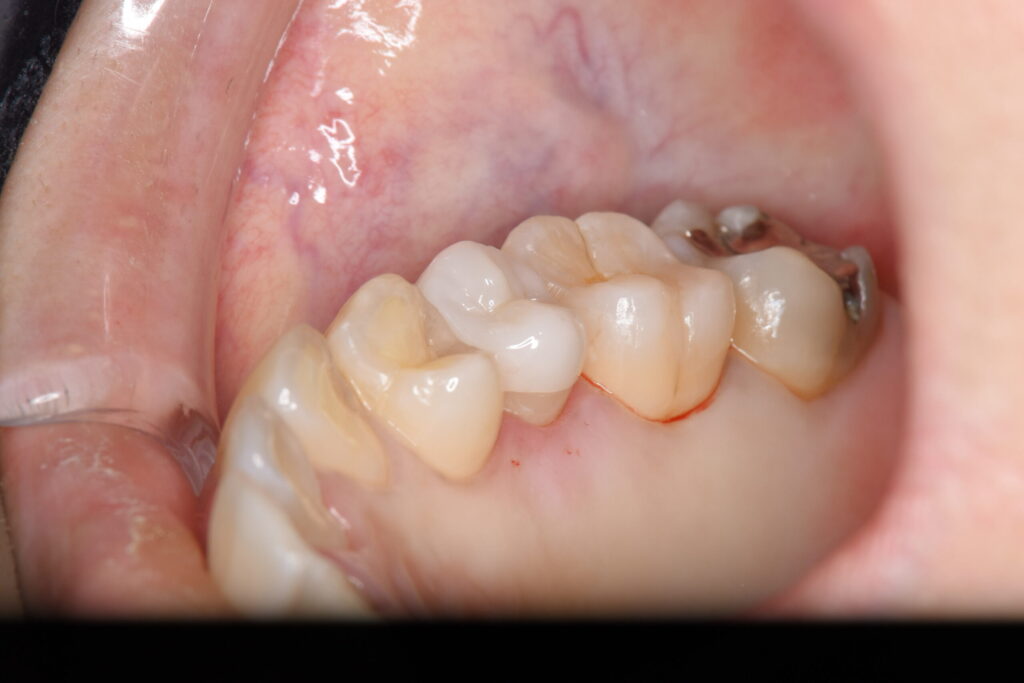

被せ物の試適です。隙間がないことが確認できたため接着を行いました。

| 銀歯の下の虫歯の再発をVPT治療(歯髄温存療法)を行なったのち、ジルコニアの被せ物にて補綴処置を行なった。 |

| VPT歯髄温存療法1回、ジルコニアによる補綴処置2回 |